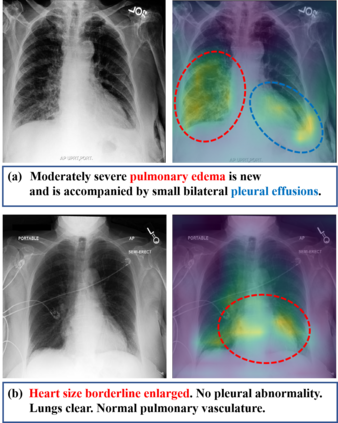

Recently a number of studies demonstrated impressive performance on diverse vision-language multimodal tasks such as image captioning and visual question answering by extending the self-attention based Transformer architecture with multimodal pre-training objectives. Despite its huge potential, vision-language multimodal pre-training in the medical domain has only recently received attention, and only demonstrated improved diagnosis accuracy of vision-language pre-trained models. In this work we explore a broad set of multimodal representation learning tasks in the medical domain, specifically using radiology images and the unstructured report. We propose a new model which adopts a Transformer based architecture combined with a novel multimodal attention masking scheme to maximize generalization performance for both vision-language understanding task (e.g., diagnosis classification) and vision-language generation task (e.g., radiology report generation). By rigorously evaluating the proposed model on four downstream tasks with three radiographic image-text datasets (MIMIC-CXR, Open-I, and VQA-RAD), we empirically demonstrate the superior downstream task performance and generality of our model against various baselines including task specific architectures. In addition, we qualitatively analyze our model by showing the results of retrieved image-report pairs, the attention map visualization, and generated reports. Our proposed multimodal pre-training model could flexibly adapt to multiple downstream tasks of vision-language understanding and generation with a novel self-attention scheme. We believe that our approach can provide the basis for a wide range of interpretations of vision-language multimodal in the medical domain.